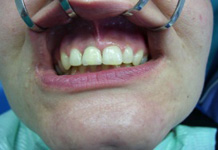

S těmito typy náhrad můžeme dosáhnout perfektní funkci, výbornou estetiku, fonetiku a současně zajistit u pacienta možnost dobré hygienickou péče a čištění, která je pro životnost implantátů velice důležitá.